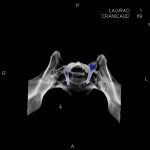

- Diagnosticul fracturilor:

- Unice

- Multiple

- Cu înfundare

- Complexe cranio-sinusale

- Complexe cranio-etmoidale

- Complexe cranio-orbitare

- Complexe cranio-faciale